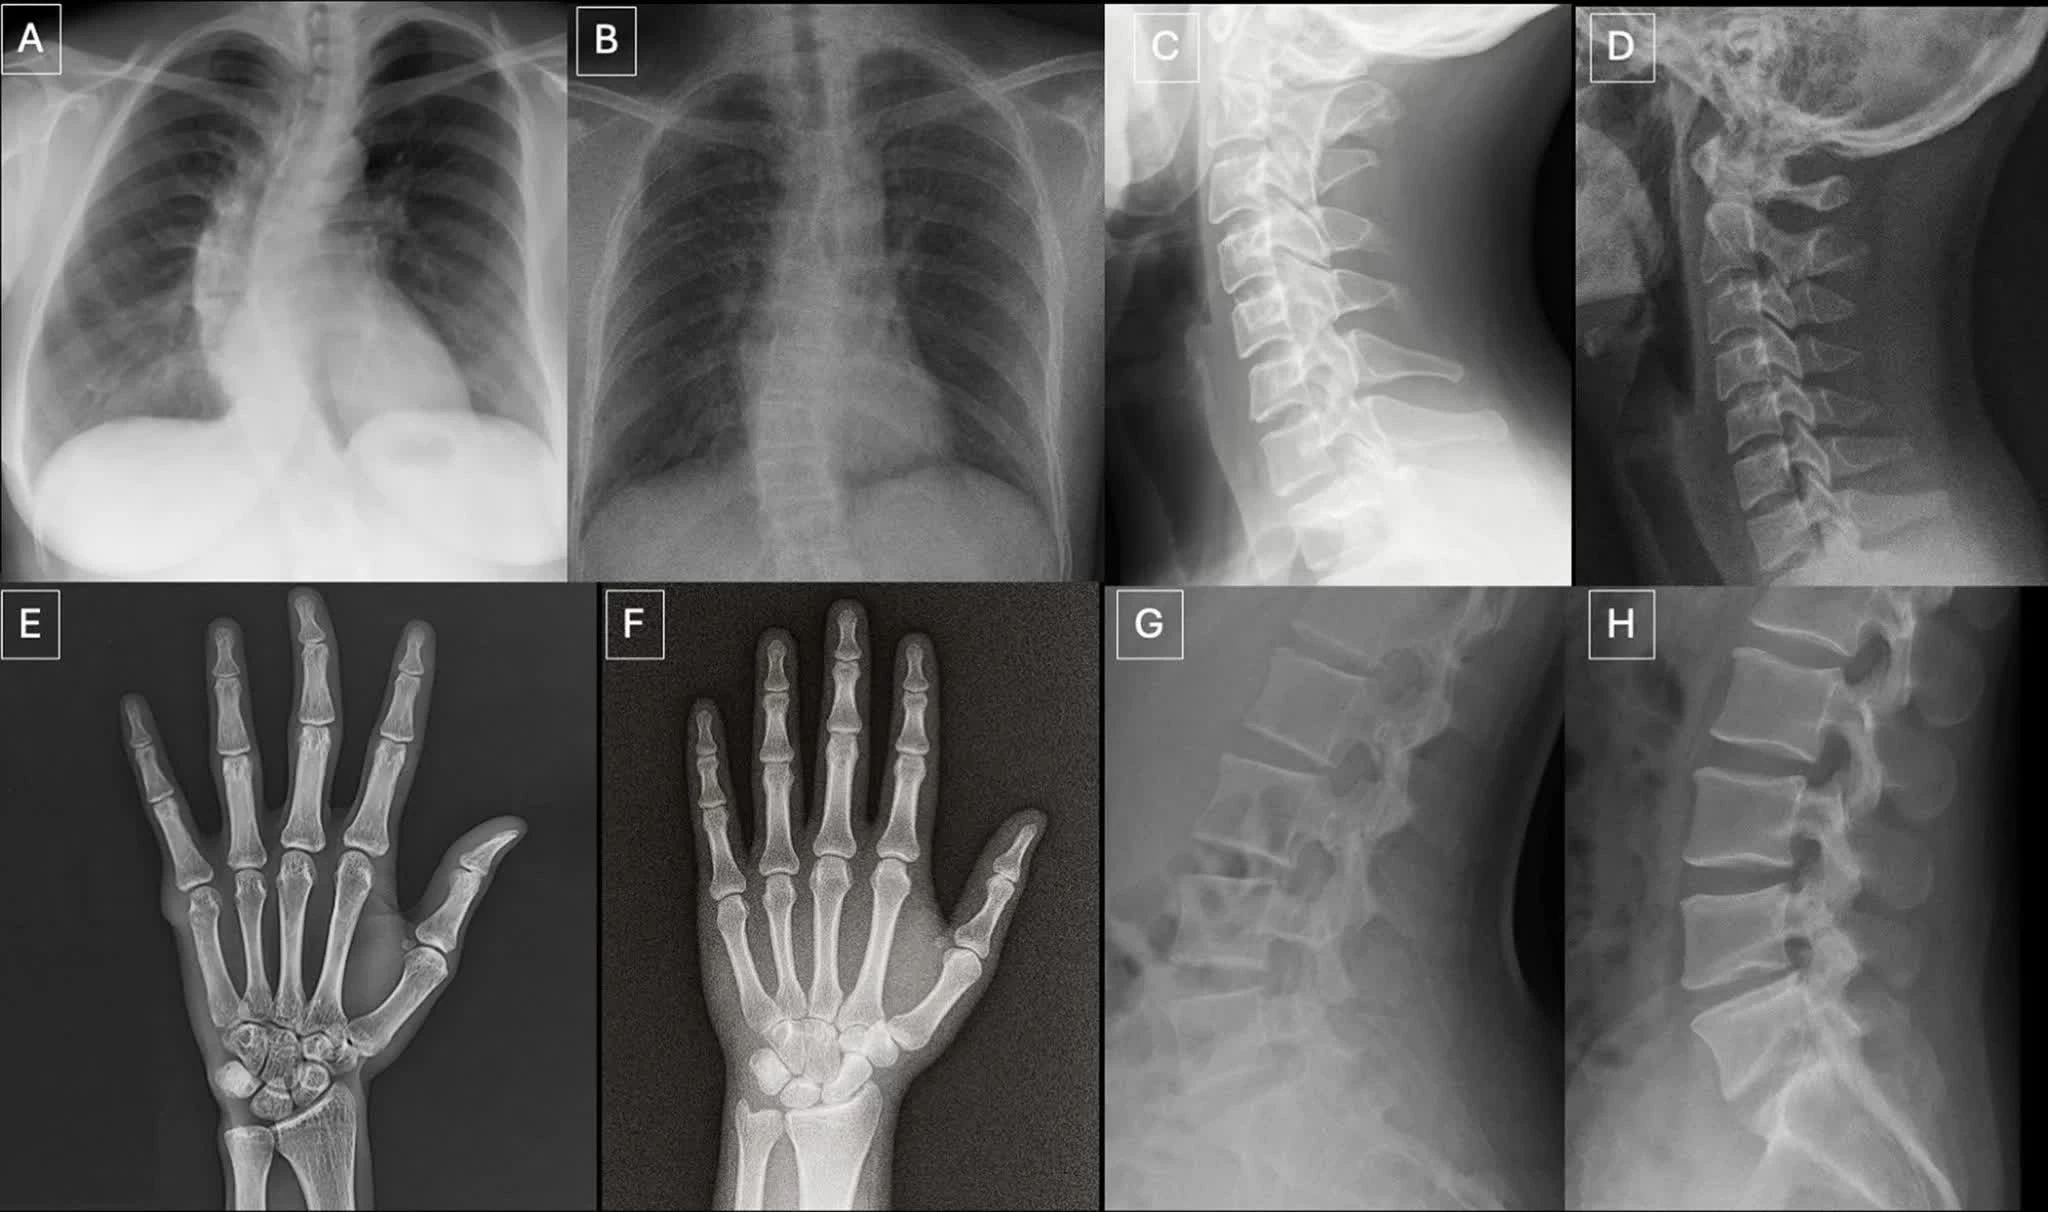

Trong tổng 264 ảnh X-quang được sử dụng trong nghiên cứu, một nửa là ảnh thật và một nửa do AI tạo ra. Các bác sĩ tham gia đánh giá hai bộ dữ liệu riêng biệt, bao gồm nhiều vùng cơ thể và một bộ ảnh X-quang phổi chuyên biệt, được tạo ra bằng các mô hình AI như ChatGPT và RoentGen.

Theo nhóm nghiên cứu, ảnh X-quang giả thường mang một số đặc điểm thị giác tinh vi như cấu trúc xương quá mịn, cột sống thẳng bất thường, phổi đối xứng hoàn hảo, mạch máu phân bố đồng đều và các vết gãy có hình dạng “quá đẹp”, thường chỉ xuất hiện ở một phía của xương.